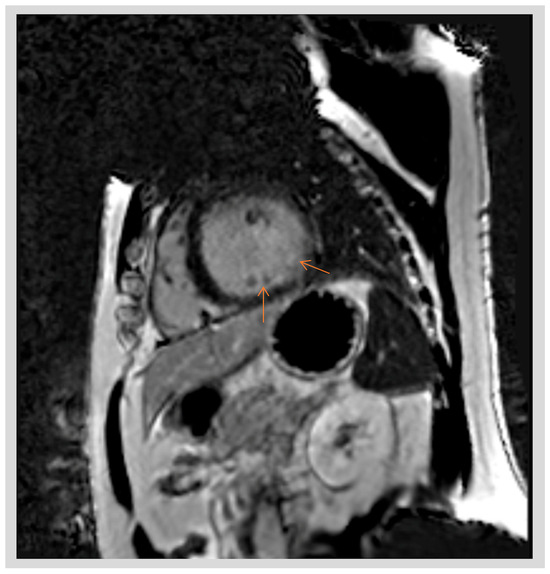

3.3. Role of Mitral Annular Disjunction in Arrhythmogenesis

- Marra, M.P.; Basso, C.; De Lazzari, M.; Rizzo, S.; Cipriani, A.; Giorgi, B.; Lacognata, C.; Rigato, I.; Migliore, F.; Pilichou, K.; et al. Morphofunctional Abnormalities of Mitral Annulus and Arrhythmic Mitral Valve Prolapse. Circ. Cardiovasc. Imaging 2016, 9, e005030. [Google Scholar] [CrossRef]

- Marra, M.P.; Cecere, A.; Cipriani, A.; Migliore, F.; Zorzi, A.; De Lazzari, M.; Lorenzoni, G.; Cecchetto, A.; Brunetti, G.; Graziano, F.; et al. Determinants of Ventricular Arrhythmias in Mitral Valve Prolapse. JACC Clin. Electrophysiol. 2024, 10, 670–681. [Google Scholar] [CrossRef]